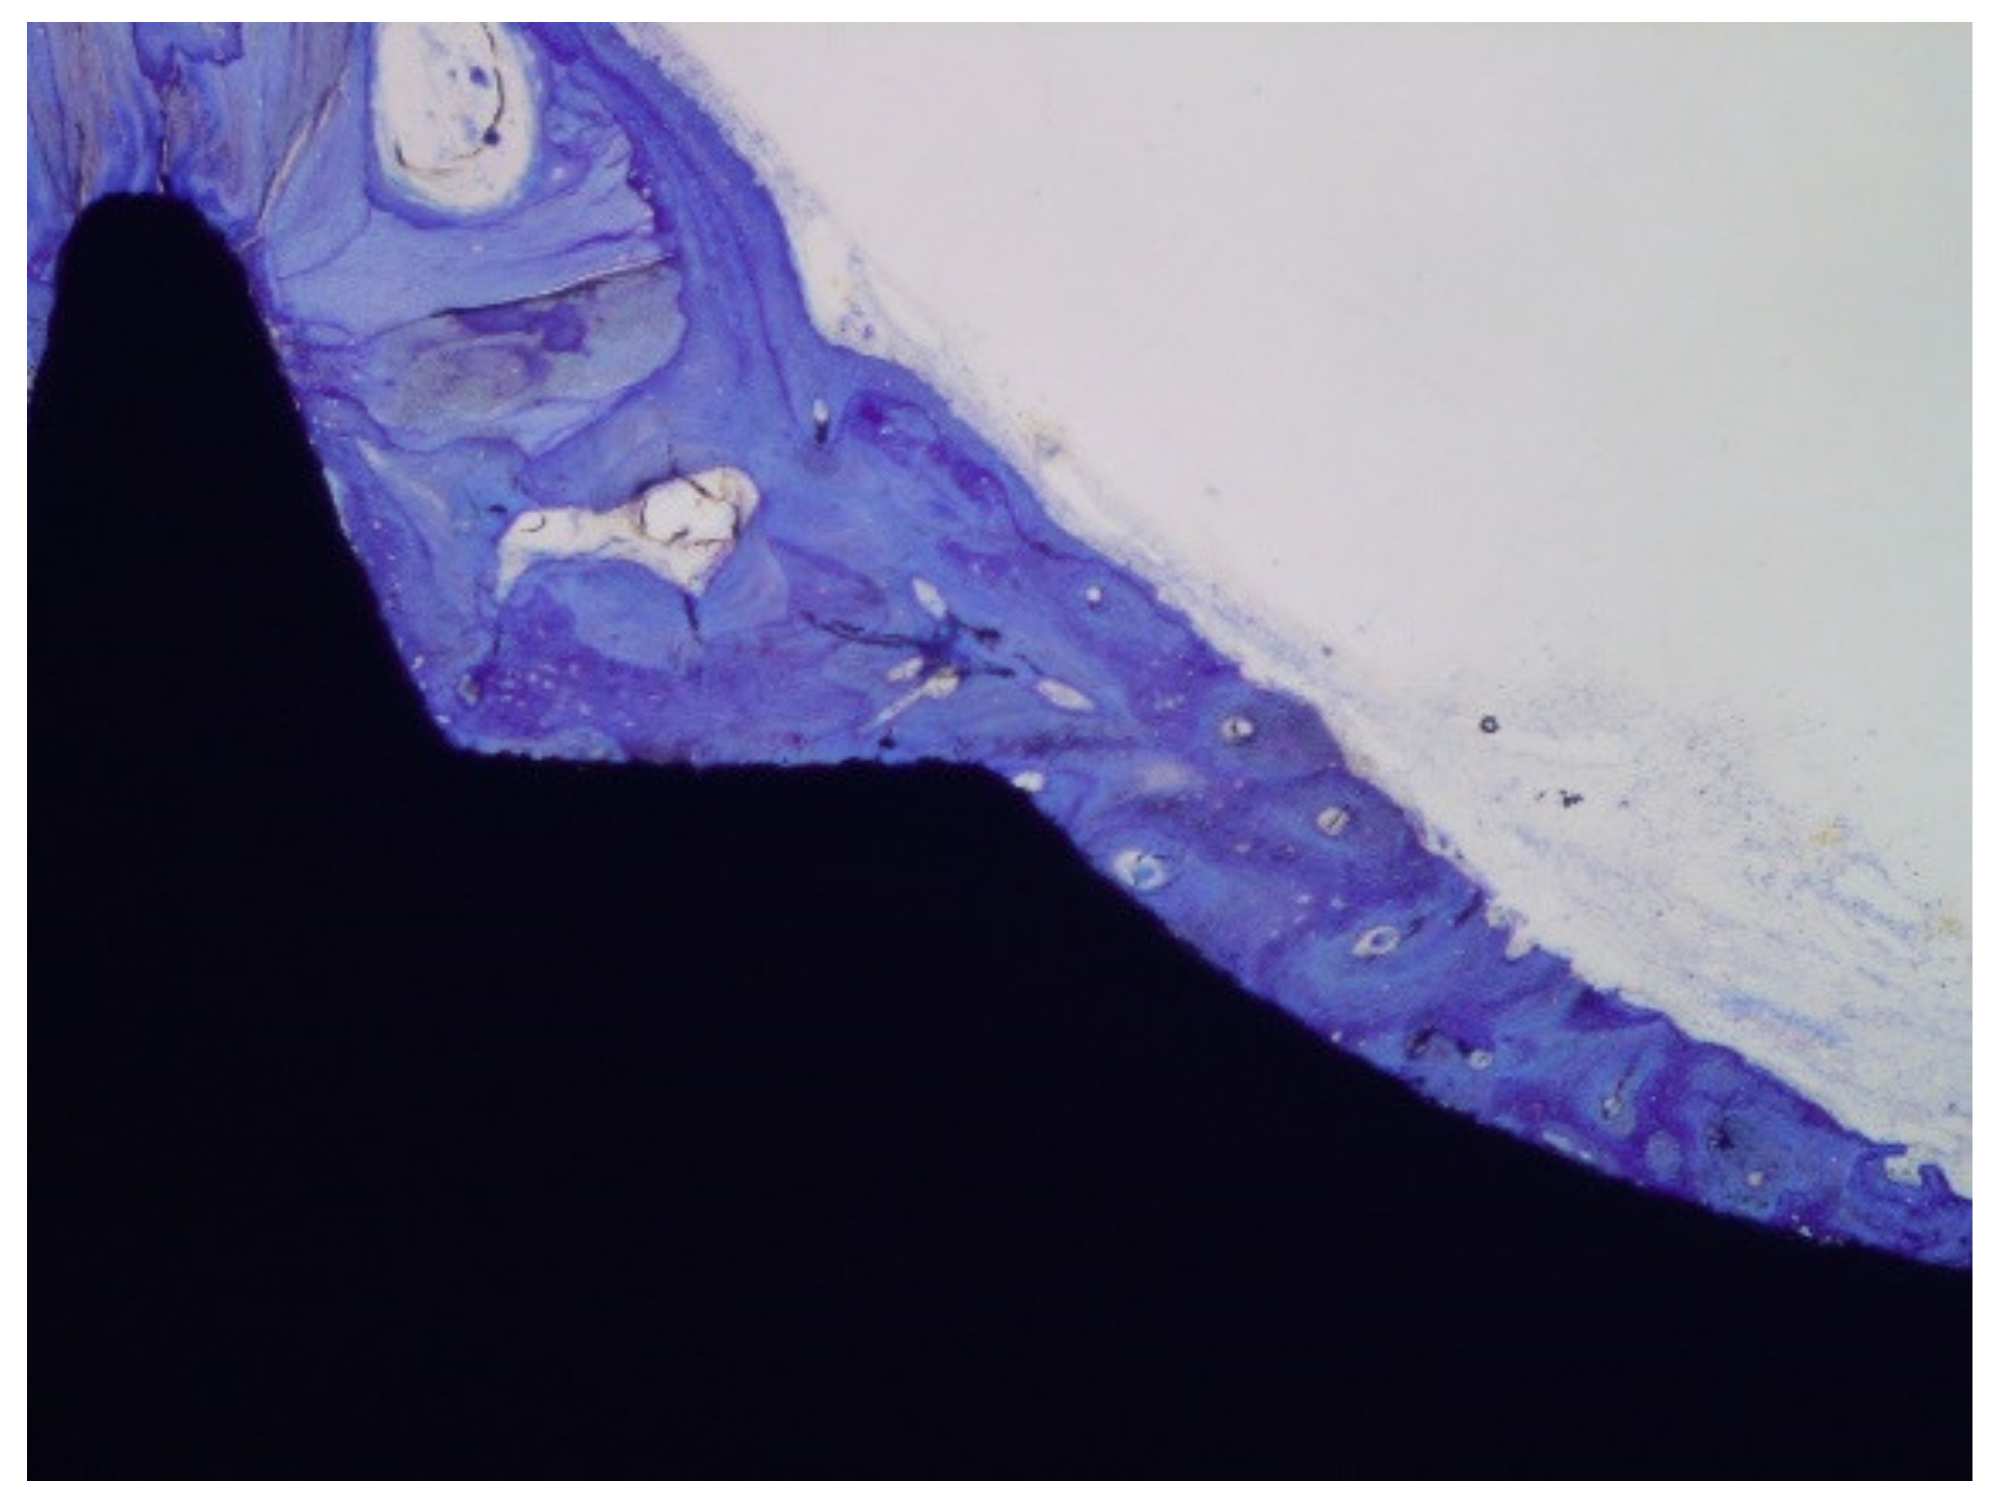

The histologies show how the implant surface facilitates the formation of bone, as shown in Figure 12 and Figure 13, and where bone is formed from the implant surface with sodium titanate. With this, an osteoinductive effect is achieved that favors the reduction in osseointegration time [47,48,49,50].

Figure 13. Histology at 2 weeks after implantation. (a). Dental implant with an osseointegration of approximately 70% after two weeks of implantation. (b). At higher magnification showing the implant-bone tissue interface.